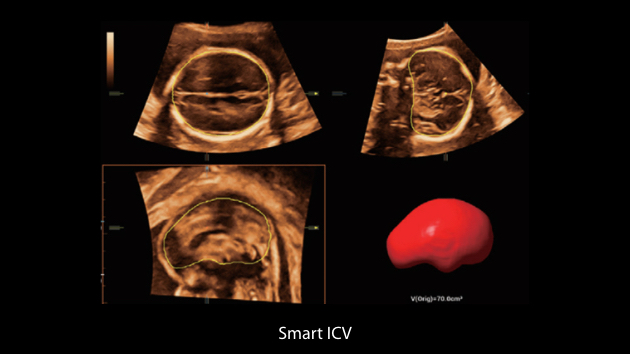

Nuewa I9? ??? ???? ?? ??? ?? ??? ???? ?? ??? ???? ???? ??? ?????. ??? ??? ??? ?? ????? ?? ???? ???? ???? ???? ??? ???? ??? ??? ???? ??? ???? ??? ?? ?????.

ZST+ ???? ???? ??? ???? ??? ?????. ??? ????? ??? ? ???? ?? ??? ?? ????? ?????. ?? ???, ?? ???, ?? ??? ?? ?? ?? ??? ??? ???? ???? ??? ?? ??? ?? ???? ?? ??? ?? ??? ?????.